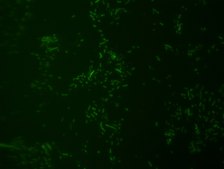

Fluorescent In Situ Hybridization technique (FISH) is based on the hybridization of fluorescent labeled oligonucleotide probe to a specific complementary DNA or RNA sequence in whole and intact cells.Microbial FISH allows the visualization, identification, and isolation of bacteria due to recognition of ribosomal RNA also in unculturable samples. FISH technique can serve as a powerful tool in the microbiome research field by allowing the observation of native microbial populations in diverse microbiome environments, such as samples from human origin (blood3 and tissue4), microbial ecology (solid biofilms5 and aquatic systems6) and plants7. It is strongly recommended to include positive and negative controls in FISH assays to ensure specific binding of the probe of interest and appropriate protocol conditions. We offer positive (MBD0032/33) and negative control (MBD0034/35) probes, that accompany the specific probe of interest. Akkermansia muciniphila probe specifically recognizes Akkermansia muciniphila cells. Akkermansia muciniphila is a gram negative, oval shaped, non-motile, non-spore forming strictly anaerobic bacteria.8 A. muciniphila inhabits the gastrointestinal tracts of more than 90% of adults and constitutes 1 to 4% of the fecal microbiota.9 It is one of the top 20 most abundant species detectable in the human gut.10 The mucus layer of the human intestine is a niche which is colonized by specific bacteria such as A. muciniphila. A. muciniphila can degrade mucin, a key mucus component, using the enzymes sialidase and fucosidase, and utilize it as a source of carbon and nitrogen.11 Consequently, the host produces additional mucus while the bacterium produces oligosaccharides and Short Chain Fatty Acids (SCFAs) that can be utilized by the host and trigger the immune system. An additional protective effect of the SCFA is stimulation of mucus-associated microbiota growth, that serves as a barrier against penetration of pathogens to intestinal cells.9,12 It was found that A. muciniphila abundance in the gut was correlated to a healthy intestine and inversely correlated to many disease conditions.11 In comparison to healthy controls, A. muciniphila levels were low in patients with intestinal disorders, such as inflammatory bowel disease (IBD), but also in other conditions, such as autism, atopy, and obesity.11,13-16 Therefore, the level of A. muciniphila was suggested to serve as a biomarker for healthy intestine.17 A. muciniphila is a promising potential probiotic that can be administrated for the treatment of diseases such as, colitis, metabolic syndromes, immune diseases, and cancer.10 FISH technique was successfully used to identify A. muciniphila with the probe in various samples such as pure culture (as described in the figure legends18), fecal samples19-21, gut lumen content22, appendix samples23, cecum content and tissue24,25 and colon tissue26. The probe can also be used for FISH coupled with flow cytometry (FCM-FISH)19,20,21, and FISH combined with Raman microspectroscopy

• Visualize, identify, and isolate Akkermansia muciniphila cells.

• Specific, sensitive, and robust identification of A. muciniphila in bacterial mixed population.

• Specific, sensitive, and robust identification even when A. muciniphila is in low abundance in the sample.

• Identify A. muciniphila in clinical samples such as, gut lumen content, appendix samples (formalin-fixed paraffin-embedded (FFPE) samples), fecal samples and colon tissue.